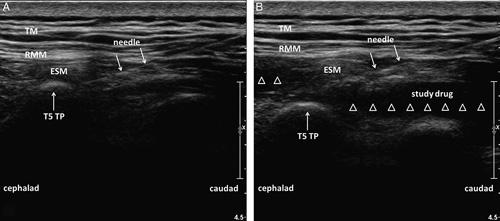

Sixty patients with esophageal cancer were randomized to receive ESPB using 28 mL of 0.5% ropivacaine, with 2 mL of normal saline (group R) or 0.5 µg/kg dexmedetomidine in 2 mL (group RD) administered interfascially. ESPB was performed at the fifth thoracic level under ultrasound guidance. The primary outcome was the duration of analgesia. The secondary outcomes were total postoperative sufentanil consumption, Numeric Rating Scale pain scores, Ramsay Sedation Scale scores and adverse effects.